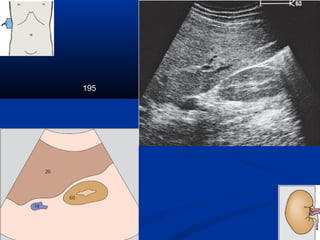

195

Kyõ thuaät : caùc maët caétKyõ thuaät : caùc maët caét